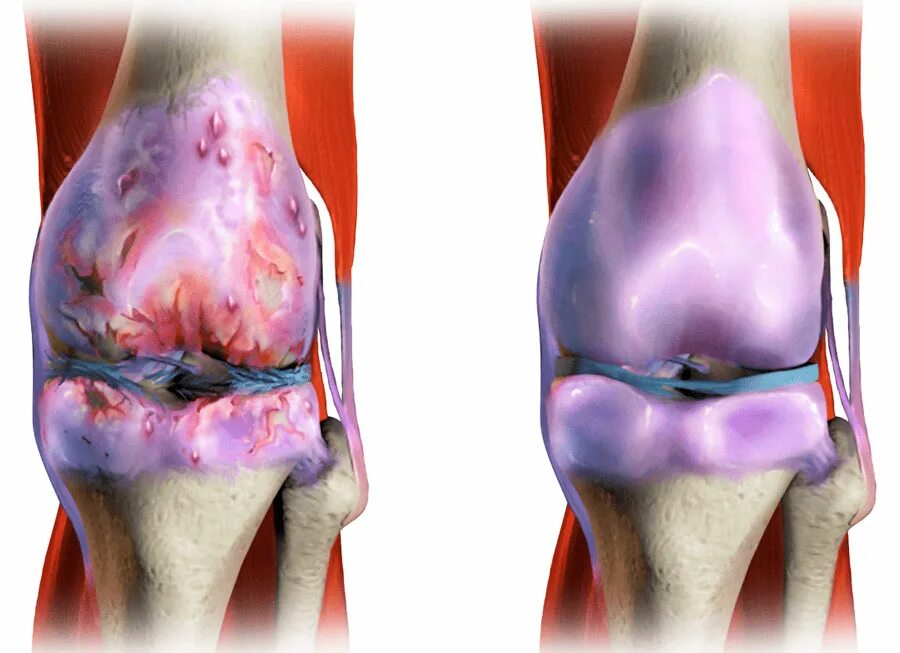

Явления остеоартроза